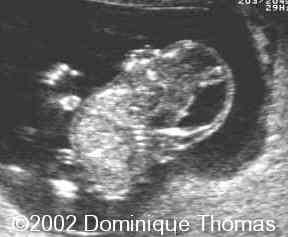

What is this an image of?

iniencephaly (star gazer position)